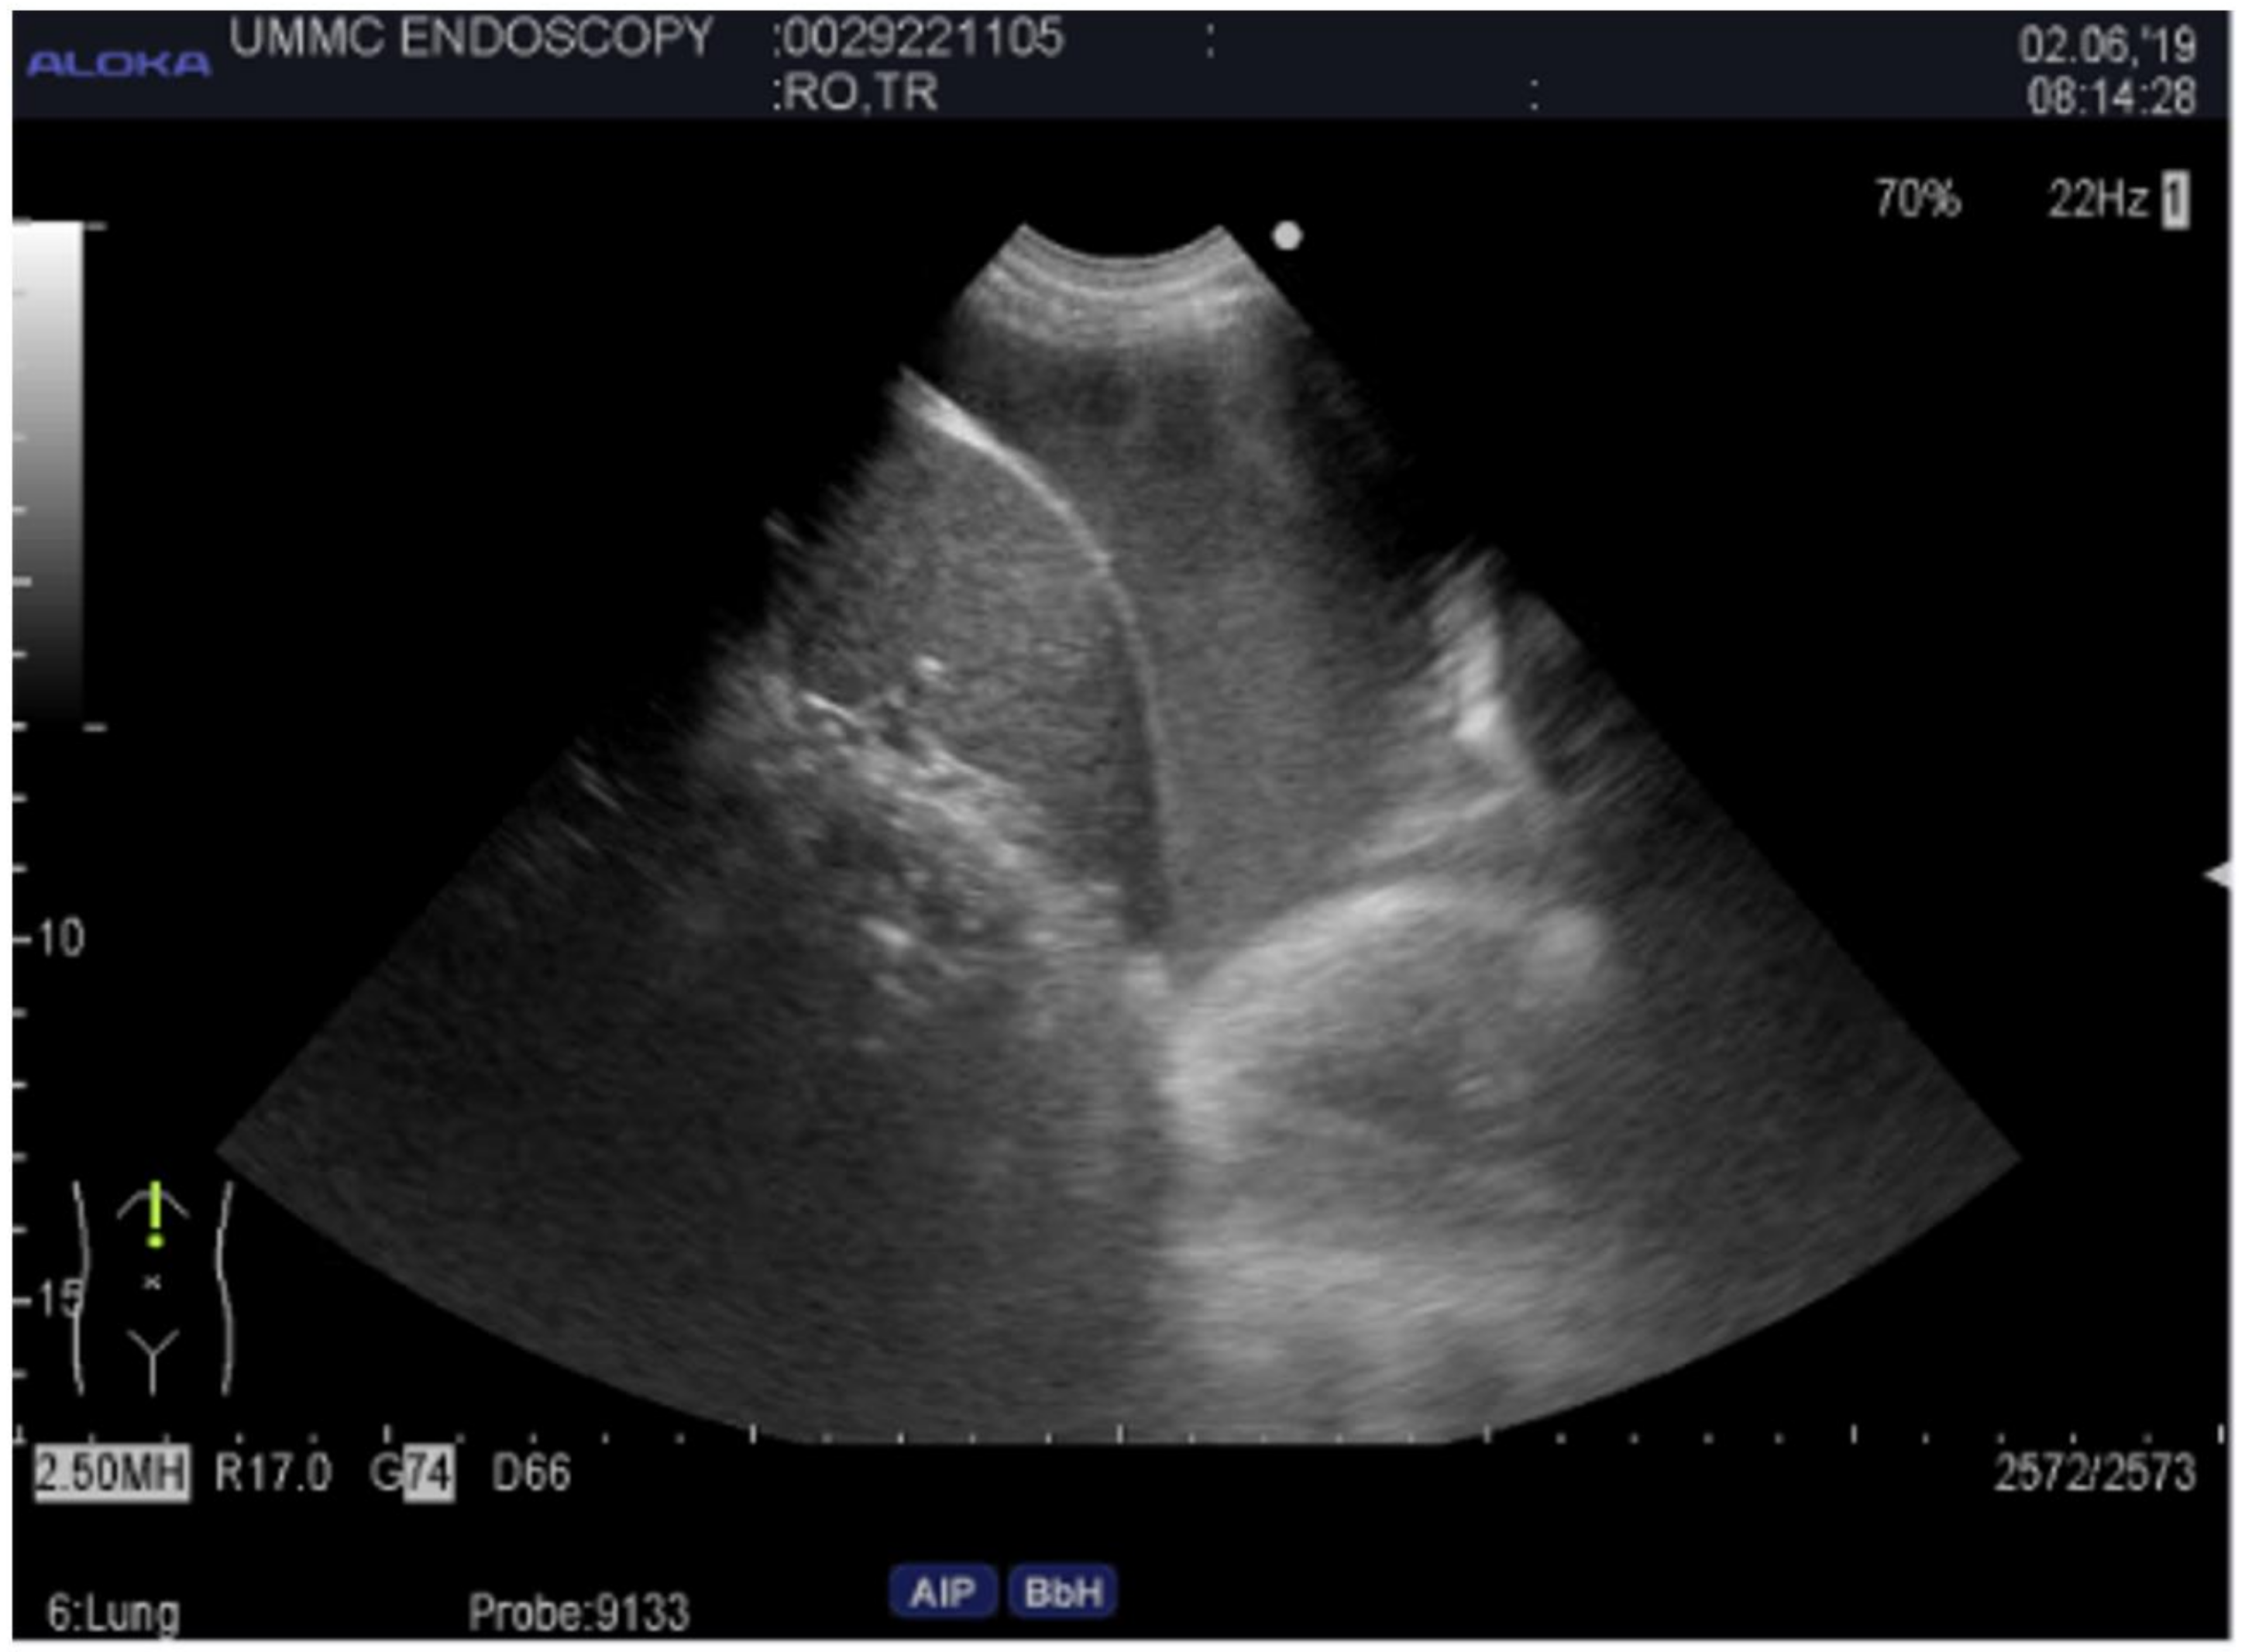

2.4. Endobronchial Ultrasound